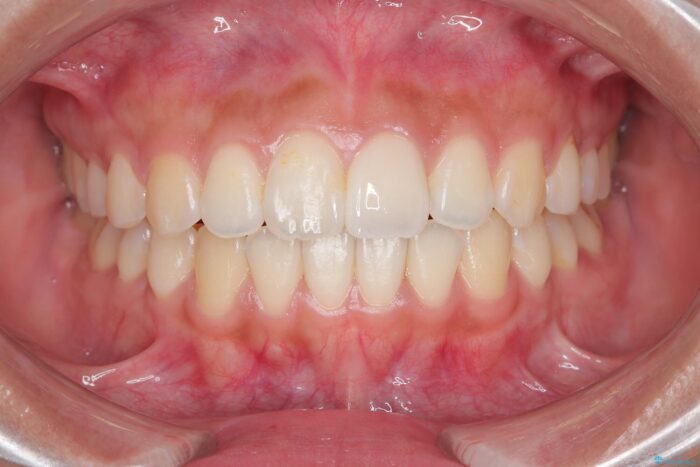

治療後について

1年で歯並び、嚙み合わせともにしっかりと改善されました。

患者様にも、非常に噛みやすくなったと喜んでいただくことができました。